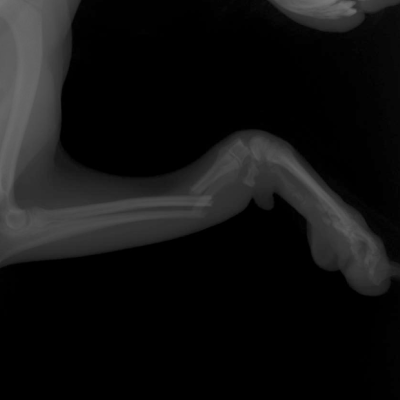

Case8症例8

橈骨骨折:1

小型犬に多い前肢の骨折です。交通事故ではなく、家の中の少し高いところから飛び降りた時に骨折してしまうことが多いです。

この症例は骨が細すぎてプレートの適用が難しいため、ピンニングという手法を使いました。(体重:2.4kg)

ピンの直径は0.8mm、これだけではすぐに曲がってしまうためギプスを使用して運動制限をします。

すぐに帰宅してしまうと運動制限がうまくできず再骨折や接合部が曲がってしまう可能性が高いため、約一ヶ月入院させてケージ内で運動制限を行いました。

術後は三ヶ月ギプスの補助固定を継続し、その後レントゲンを撮影して骨の治癒を確認してからピンを抜きました。